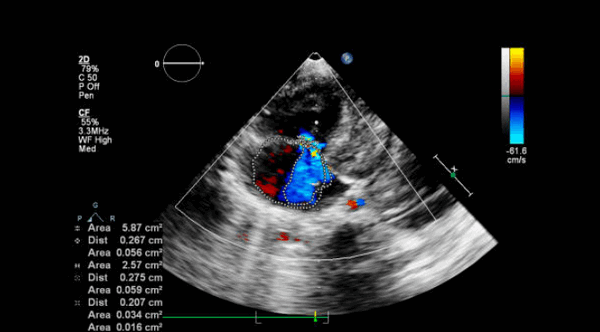

Регургитация. Она может происходить через отверстие клапана (чрезклапанная) или вокруг пришивного кольца (парапротезная). Легкая транскалапанная митральная регургитация может быть обнаружена в нормально функционирующих клапанах, чаще в механических клапанах. Это связано с закрытием клапана или из-за зазоров между разными частями протеза. Ее бывает трудно обнаружить из-за маскировки тенью протеза. Умеренная или тяжелая митральная регургитация всегда считается патологической.

Непрерывно-волновой допплер более полезен, чем импульсный, а цветное допплеровское картирование кровотока (ЦДК) хорошо для отображения антероградных и ретроградных потоков. Турбулентный кровоток регистрируется в виде мозаики цветов. В митральных биопротезах обычно видна одна струя. В большинстве митральных механических клапанов видны 2 струи (почти равного размера у клапанов Старра - Эдвардса, одна меньше другой в клапанах Бьорка - Шайли).

При регургитации может быть несколько струй разного размера в зависимости от типа клапана (например, 2 струи у Бьорка - Шили, несколько у Старра - Эдвардса). ЦДК также помогает различать чресклапанную и парапротезную регургитацию и помогает выявить новую регургитацию.